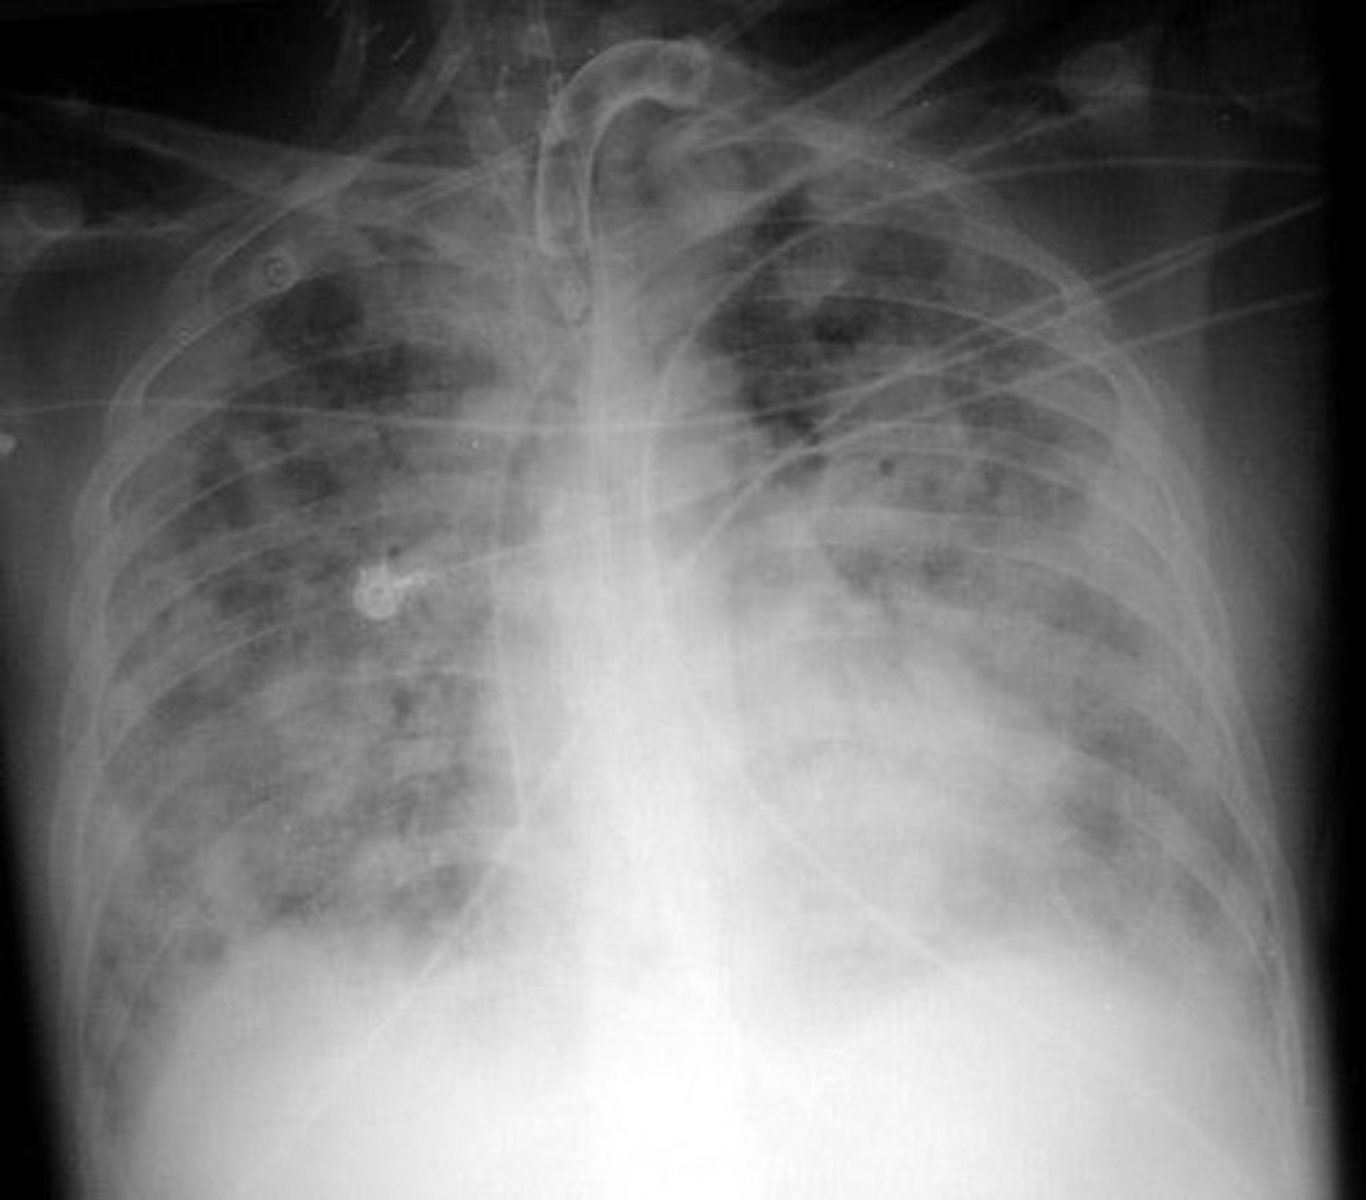

Covid pneumonia acute respiratory distress syndrome

Condition where one lung would be whited out with fluid

Proning

Practice that displaces fluid and increases perfusion to different areas of the lung